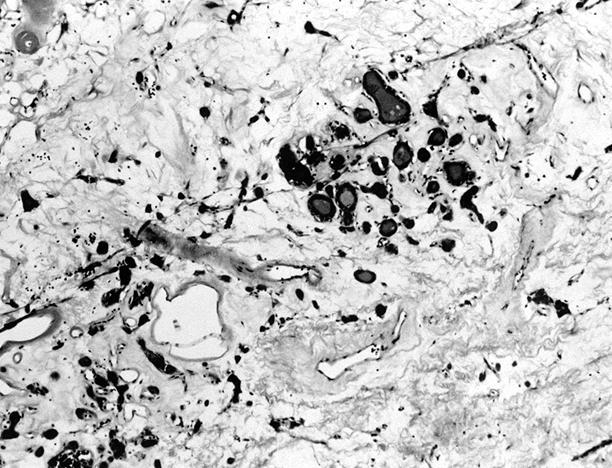

Microscopic (histologic) images

Contributed by Shipra Agarwal, M.D., Andrey Bychkov, M.D., Ph.D., Mark R. Wick, M.D., Asmaa Gaber Abdou, M.D. and AFIP

- Secondary changes: fibrosis, hyalinization, hemorrhage, hemosiderin deposition, edema, cystic degeneration, calcification, osseous or cartilaginous metaplasia

- Black follicular adenoma (black pigment in tumor cell cytoplasm; in patients on minocycline therapy)

- Rarely black; especially seen with minocycline therapy